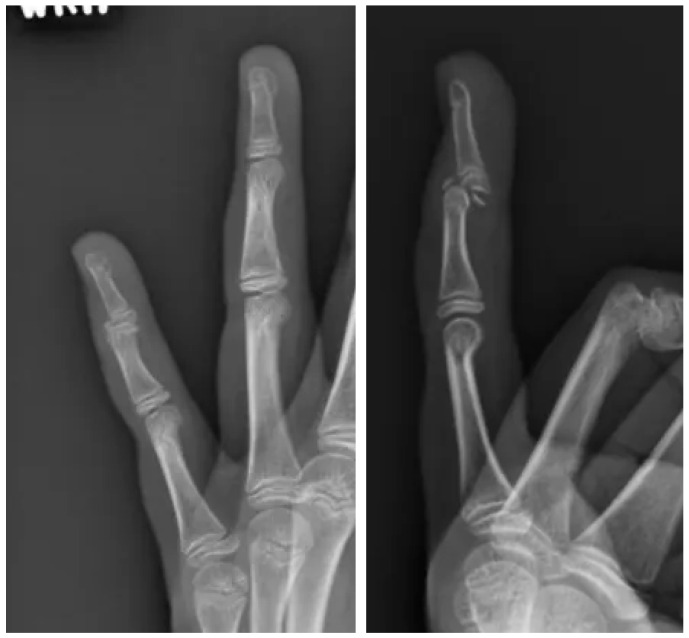

手指损伤在儿科患者中很常见,保守治疗通常愈合良好。然而,罕见的骨折类型涉及明显的移位和物理损伤,如本例所述,需要专门的手术干预,以确保适当的愈合和防止长期并发症。病例介绍:一名12岁的女性,以左手为主,表现为左第五指过伸后的远端指间关节疼痛、肿胀和畸形。最初的x线片显示掌侧移位的关节内骨折伴物理受累,经计算机断层扫描(CT)成像证实。保守治疗与闭合复位和夹板未能达到适当的对准。手术干预通过背侧入路进行,利用ORIF与k针固定来恢复关节一致性并确保解剖对准。结果:术后随访显示满意的愈合,保持复位,疼痛缓解,无并发症。患者以最小的僵硬度恢复了手指的功能使用,生长板在恢复期间未受累。讨论:本病例强调了先进影像学、早期转诊和量身定制的手术干预对罕见槌状骨折伴掌侧移位和物理损伤的重要性。在这个复杂的病例中,ORIF提供了可靠的稳定和最佳的结果。结论:掌侧移位的Salter-Harris III型DIP关节骨折是儿科患者罕见且具有挑战性的损伤。该病例强调了ORIF在获得成功结果中的作用,并强调了精确复位和稳定以防止长期并发症的重要性。

Introduction: Finger injuries are common in pediatric patients and typically heal well with conservative management. However, rare fracture patterns involving significant displacement and physeal injury, such as the one described in this case, require specialized surgical intervention to ensure proper healing and prevent long-term complications. Case Presentation: A 12-year-old left-hand-dominant female presented with pain, swelling, and deformity at the distal interphalangeal (DIP) joint following hyperextension of the left fifth digit. Initial radiographs revealed a volar displaced intra-articular fracture with physis involvement, confirmed by computed tomography (CT) imaging. Conservative management with closed reduction and splinting failed to achieve adequate alignment. Surgical intervention was performed via a dorsal approach, utilizing ORIF with K-wire fixation to restore joint congruity and ensure anatomic alignment. Outcomes: Postoperative follow-up demonstrated satisfactory healing, maintained reduction, and resolution of pain with no complications. The patient regained functional use of the digit with minimal stiffness, and the growth plate remained uninvolved during the recovery period. Discussion: This case underscores the importance of advanced imaging, early referral, and tailored surgical intervention for rare mallet fractures involving volar displacement and physeal injury. ORIF provided reliable stabilization and optimal outcomes in this complex case. Conclusions: Volar displaced Salter-Harris III fractures of the DIP joint are rare and challenging injuries in pediatric patients. This case highlights the role of ORIF in achieving successful outcomes and emphasizes the importance of precise reduction and stabilization to prevent long-term complications.